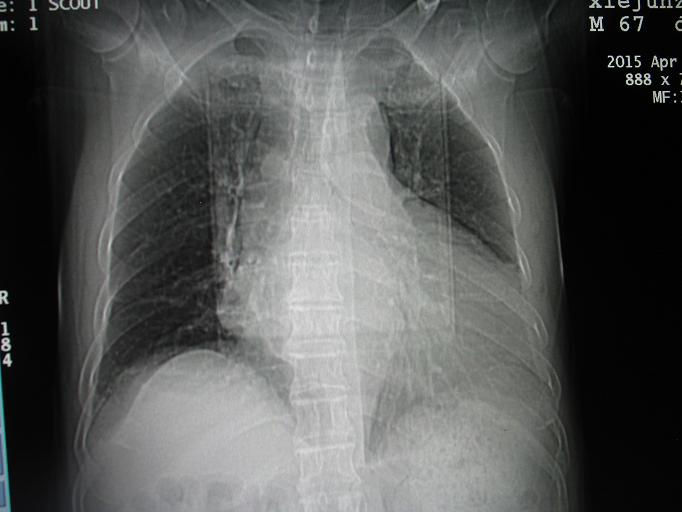

CT50327:胸部CT

下部层面究竟是胸水还是有腹水?

心衰并胸水、腹水形成

心包少量积液

心影增大,以左房室增大为主,两侧胸腔,肝周及心包见少量液体密度,考虑:心脏病,结合临床心超,胸腹水,心包积液。

心脏病,肺淤血,胸水,腹水,少量心包积液

胸水,腹水,少量心包积液。

胸水,腹水